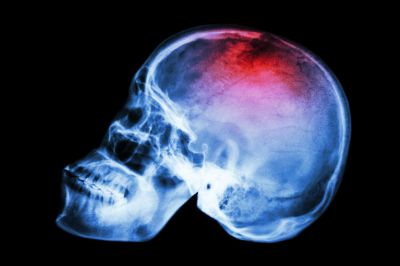

Названы наиболее эффективные классы препаратов при нелобарном внутримозговом кровоизлиянии